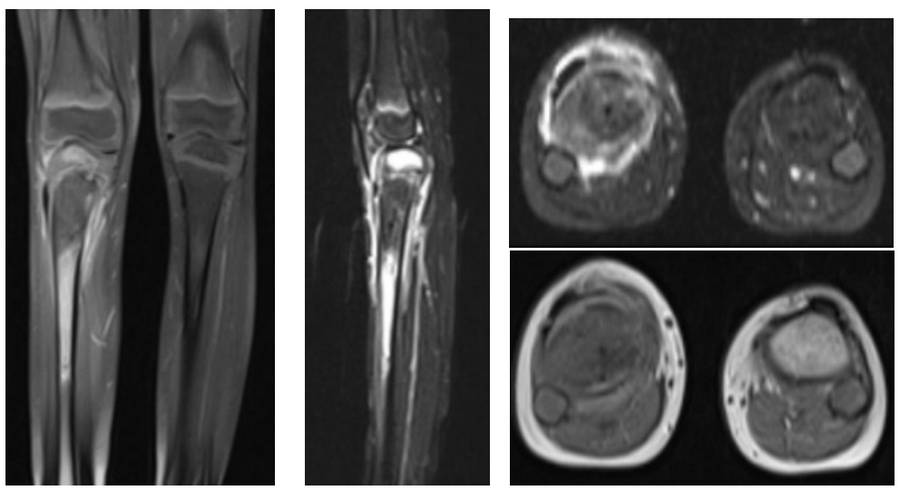

Ameliyat Öncesi: MR’da ek olarak çevreleyen yaygın ödem görülmekte